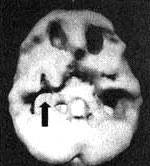

Трехмерное изображение поверхности, вид снизу. Мозг 16-летнего молодого человека, употреблявшего марихуану каждый день на протяжении двух лет; обратите внимание на многочисленные области выраженного снижения активности, особенно в височных долях (стрелки).

Единственным нарушением, выявленным у пациентов контрольной группы (СДВ), оказалась сниженная активность префронтальной коры (в 8 случаях из 10). Приблизительно такая же частота случаев сниженной активности префронтальной коры наблюдалась и в основной группе (в 25 из 30 случаев — 83 %). Однако в этой группе поражение префронтальной коры носило гораздо более выраженный характер. Кроме того, у 24 пациентов основной группы было выявлено снижение активности височных долей: у пяти из них (21 %) степень поражения оценивалась как тяжелая, у семи (29 %) — средней тяжести и у 12 (50 %) — как легкая. Тяжелая и средняя степень поражения височных долей была выявлена у тех, кто в течение последнего года курил марихуану минимум четыре раза в неделю. Однако длительность употребления наркотика в данном случае роли не играла. Один из наиболее тяжелых случаев нарушения перфузии височных долей мы обнаружили у подростка, который на протяжении двух лет курил марихуану ежедневно. У четырех пациентов был выявлен синдром отсутствия мотивации (ярко выраженное отсутствие интереса, мотивации и энергии). У всех четверых наблюдалась сниженная перфузия в височных долях, причем в трех случаях нарушение перфузии было классифицировано как тяжелое и в одном средней тяжести.

Результаты этого исследования подтвердили выводы, к которым пришли авторы предыдущих работ: частое употребление марихуаны на протяжении длительного периода времени может отрицательно сказываться на мозговом кровообращении. Если предыдущие исследования выявили общее снижение активности мозга, то нам удалось обнаружить еще и очаговое поражение височных долей (очевидно, за счет использования нами более совершенной аппаратуры). Нарушение активности височных долей вызывает проблемы с памятью, обучением и мотивацией — стандартный набор жалоб, который можно услышать от подростков (или хотя бы от их родителей) и взрослых, употребляющих марихуану на протяжении нескольких лет. У подростка, курившего марихуану каждый день на протяжении двух лет, был выявлен один из самых тяжелых случаев нарушения работы височных долей. Его симптомы соответствовали картине синдрома отсутствия мотивации, а сам он в 11-м классе бросил школу.